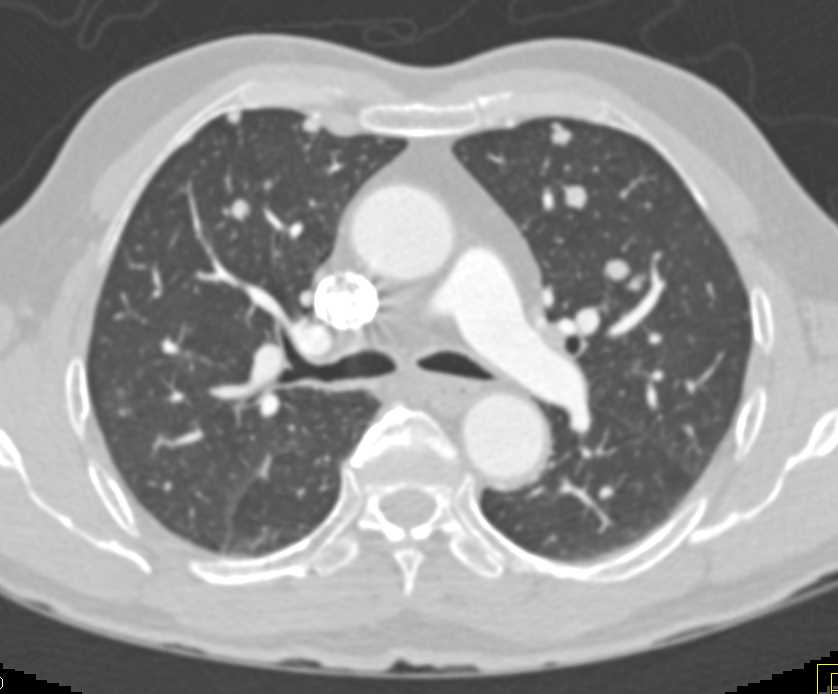

Lymphoma with Adrenal and Liver and Lung Involvement